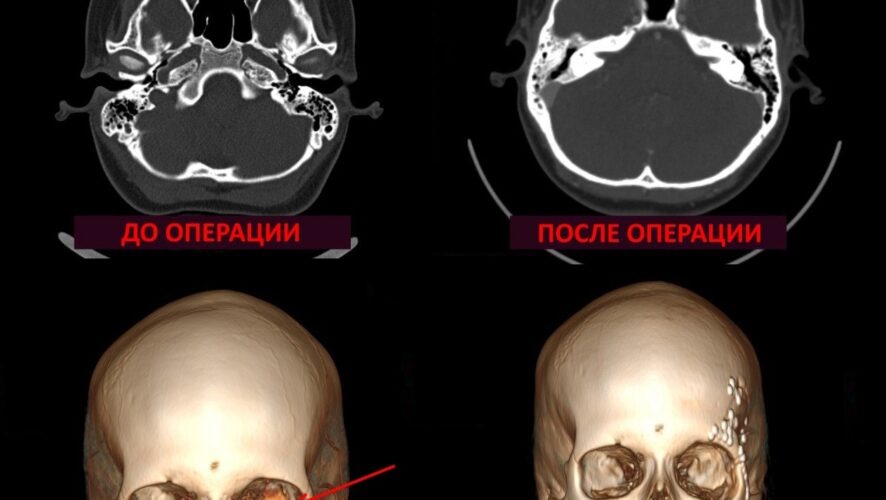

Двенадцатилетняя девочка из Республики Татарстан успешно перенесла сложнейшую операцию по удалению редкого новообразования в глазнице в Российской детской клинической больнице (РДКБ) Минздрава России. Опухоль быстро росла, смещая глазное яблоко и угрожая потерей зрения. Благодаря своевременному и высокопрофессиональному вмешательству, зрение ребенка удалось сохранить. Об этом сообщает пресс-служба РДКБ. Изначально новообразование было обнаружено врачами в Татарстане. Поскольку опухоль активно увеличивалась в размерах, девочку направили в РДКБ в Москву для более детального обследования и специализированного лечения. Первоначально предполагалось, что это сосудистая мальформация – аномалия развития сосудов. Однако специалисты отделения рентгенохирургических методов диагностики и лечения РДКБ выяснили, что, хотя опухоль и питалась от крупных артерий, она не являлась сосудистой аномалией. Это означало, что стандартные методы лечения сосудистых мальформаций не подходили, а единственным вариа

Опухоль располагалась глубоко в глазнице, в непосредственной близости от зрительного нерва и жизненно важных сосудов. Любое повреждение этих структур во время операции могло привести к слепоте.

Опухоль располагалась глубоко в глазнице, в непосредственной близости от зрительного нерва и жизненно важных сосудов. Любое повреждение этих структур во время операции могло привести к слепоте. Поэтому для проведения вмешательства была собрана междисциплинарная команда высококвалифицированных хирургов: челюстно-лицевых хирургов, нейрохирурга и офтальмолога.

Операция требовала ювелирной точности и слаженной работы всей команды. Каждый специалист выполнял свой этап: нейрохирург обеспечил доступ к опухоли, челюстно-лицевые хирурги создали операционное поле, а офтальмолог контролировал сохранность зрительного нерва и глазных мышц. После перевязки питающих опухоль сосудов, хирурги полностью удалили новообразование.

Последующее гистологическое исследование показало, что опухоль представляла собой ангиоидную гистиоцитому – доброкачественное, но быстрорастущее новообразование.

Послеоперационный период прошел без осложнений. Зрение девочки полностью сохранилось, подвижность глаза восстановилась, а смещение глазного яблока значительно уменьшилось. Юная пациентка будет находиться под наблюдением специалистов РДКБ для контроля и предотвращения возможного рецидива.